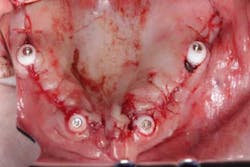

Surgery commenced. Implants on the lower arch were placed first (figures 7 and 8) and then we switched to the maxillary. The teeth were removed (figures 9 and 10) and the ridge was evened out (figures 11-13). The implants were aligned with the denture (figure 14) and then placed accordingly (figures 15-17). Healing caps were put on, and we were ready to start the restorative phase (figures 18-19).